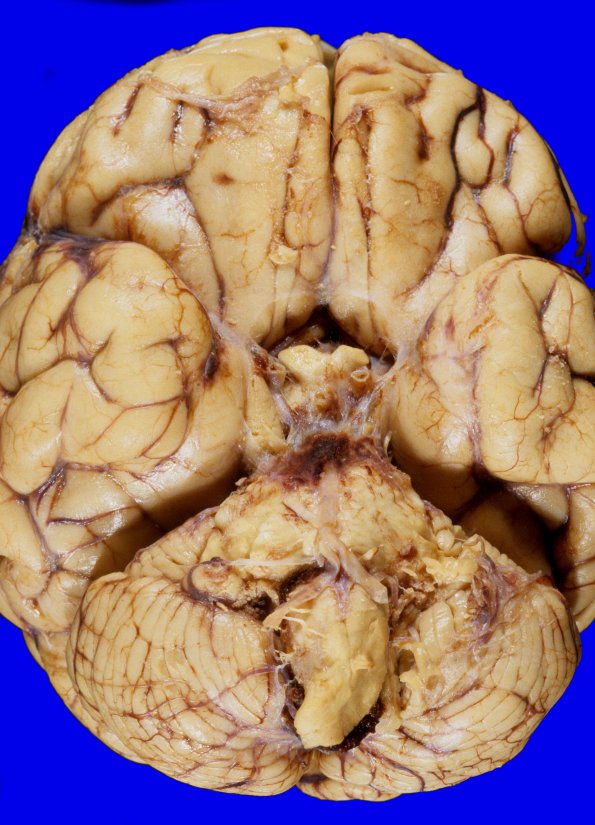

Granulocytic Sarcoma

2A1 Hemorrhage (Case 2) 4

The gyri of the temporal lobe are flattened with apparent slight grooving of the unci.